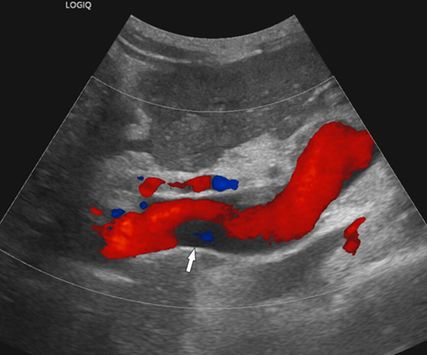

Abb. 2: Die Kontrastmittel-verstärkte MDCT (koronale 3D-Rekonstruktion) kann das Ausmaß einer PVT exakt abbilden: Die Thrombose ist nur im Pfortaderhauptstamm lokalisiert (Pfeil)

Die bildgebende Diagnostik stützt sich auf die farbcodierte Duplexsonografie (Abb. 1), die Kontrastmittel-verstärkte MDCT (Abb. 2) und die MRT, wobei die MDCT die höchste Aussagekraft hinsichtlich Ausdehnung der PVT und Darstellung möglicher Komplikationen hat. Wichtig ist bei der MDCT die Anfertigung von 3D-Rekonstruktionen des MDCT-Datensatzes zur besseren Darstellung der Thromboseausdehnung (Abb. 2), im Vergleich zur ausschließlichen Darstellung auf axialen Bildern.